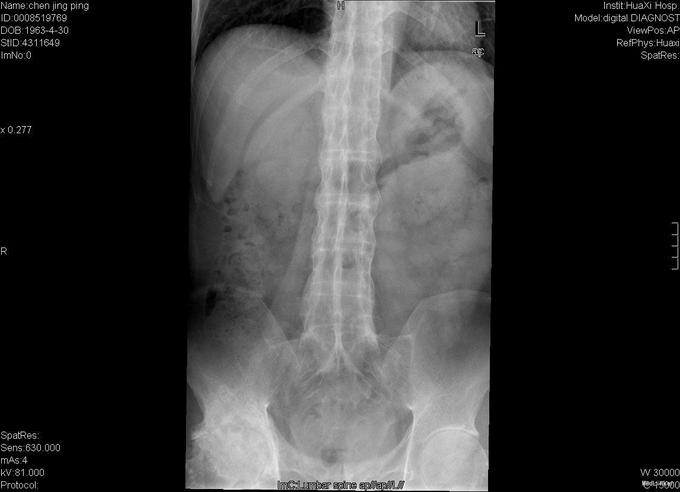

查体:跛行步态,强迫体位,脊柱强直后凸畸形,活动受限。右髋强直畸形,压痛、叩痛,无瘢痕、窦道,无皮损、皮癣,活动受限。双下肢感觉无明显异常。 辅助检查:x线片:脊柱呈"竹节样"改变,腰椎小关节间隙模糊,双侧骶髂关节及右髋关节间隙消失,骨性融合。